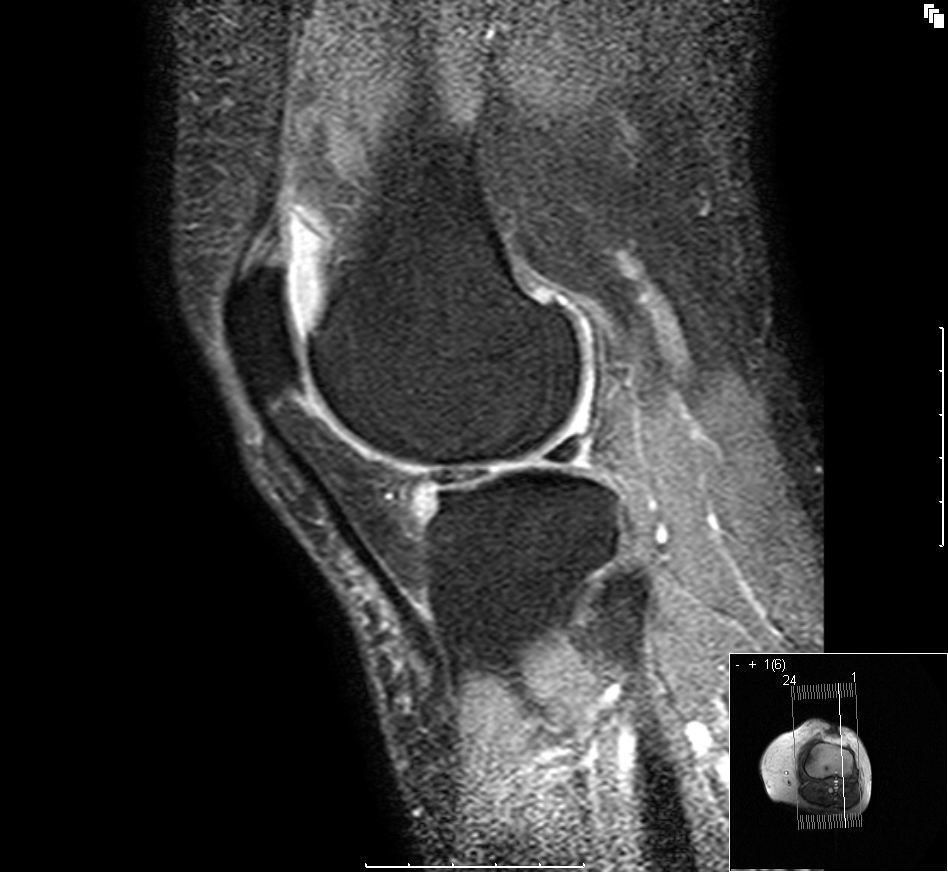

Reizerguss, NMR-Bild einer Kniearthrose im Längsschnitt.

Foto: User:Scuba-limp

Lizenz: GFDL